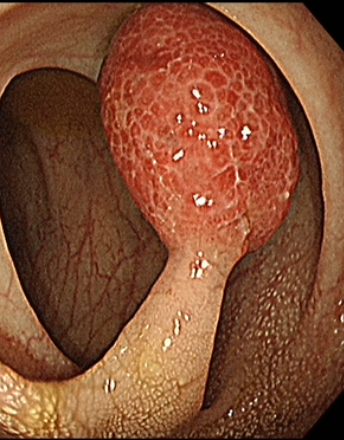

Colonic bleeding induced by a solitary juvenile polyp

A 30-year-old woman presented with 6-month history of blood-stained stools. The patient denied a family history of colon cancer. Examination was remarkable for blood-streaked stool.